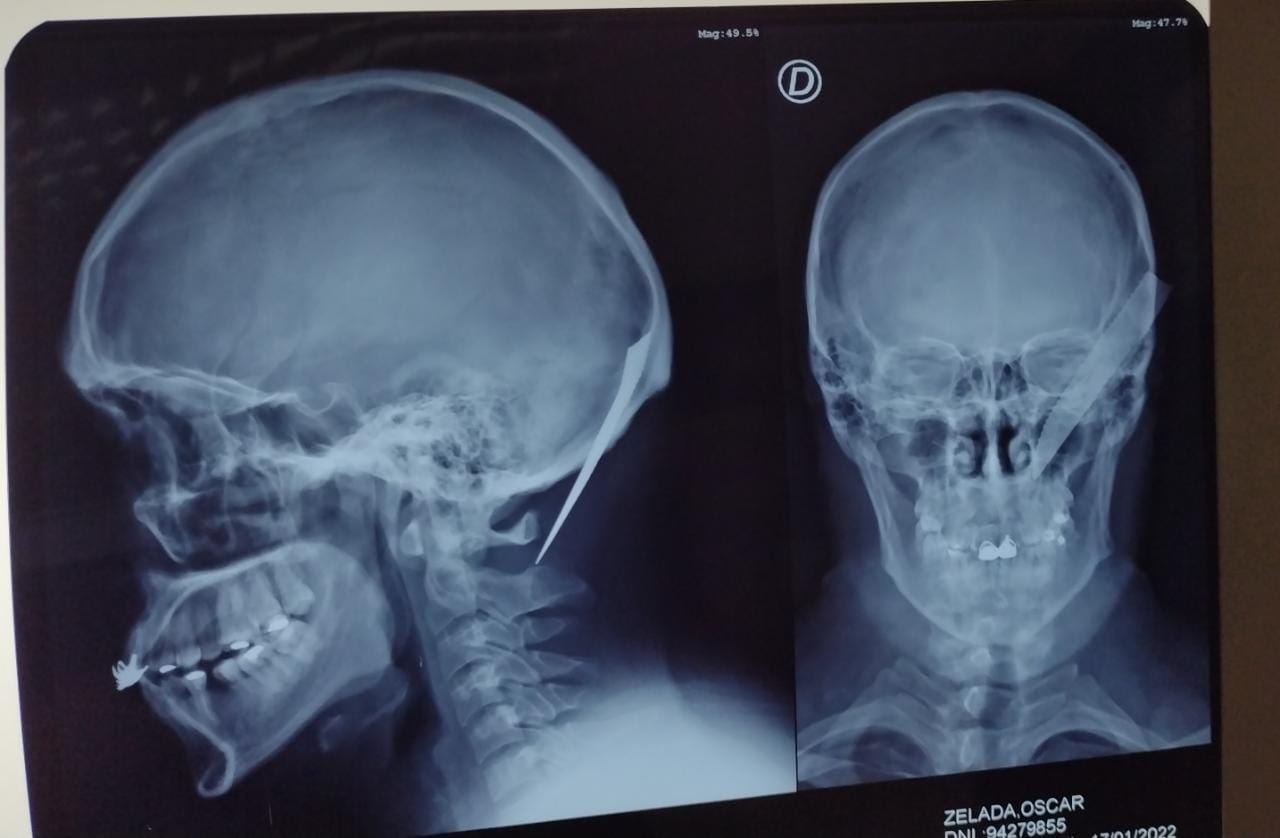

A las 23 horas ingresó al hospital un hombre con golpes en su cuerpo y un cuchillo clavado en el cráneo. La víctima fue identificada como Oscar Zelada Jaldin, de 28 años, quien relató que se encontraba en su casa con su pareja, de 17 años, cuando golpeó la puerta su prima. Al salir, recibió un golpe con un palo en la cabeza y en ese momento ingresaron a la vivienda cuatro personas, a los que reconoció como sus familiares Daniela Alcocer Jaldin (40), Limber Alcocer (44), Leona Jaldin (44) y Alcides Alcocer (22), este último armado con una pistola. Acto siguiente, lo golpearon con palos y con un cuchillo. También, agredieron a su pareja, que se encuentra embarazada. En su relato, explicó que cuando huyen en su vehículo, él comenzó a seguirlos sin darse cuenta que estaba apuñalado, hasta que chocan de frente.